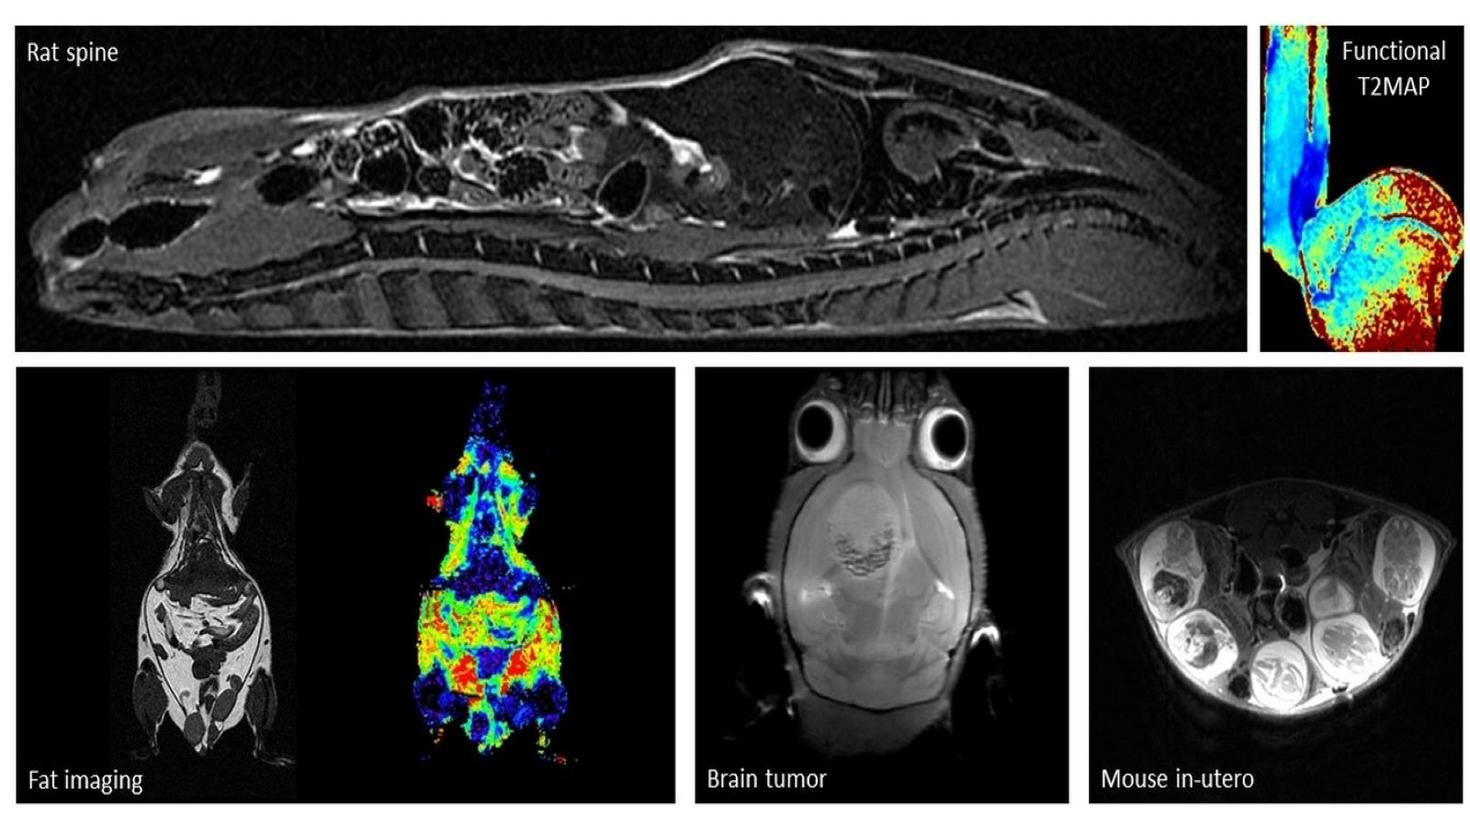

Examples of images acquired by our 7T MRI

MRI images of rat spine, brain tumor, fat imaging and mouse in-utero